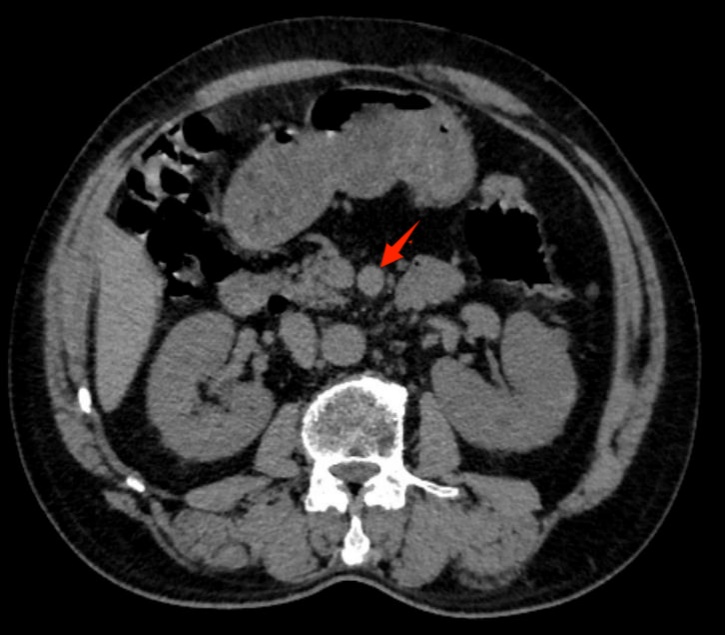

在认真查看既往检查结果和治疗经过后,龚医生建议钱先生先做一个腹部平扫CT。15:50,钱先生完成检查。很快,放射科医生钱许钧在初步阅片时,发现了一个值得警惕的细节:肠系膜上动脉有点增粗。就是这一眼,让事情开始朝着完全不同的方向发展。

影像上的异常并不总是直接给出答案,但一个经验丰富的医生,往往能从这些“不太对劲”的信号里捕捉到真正的问题。

肠系膜上动脉,是供应肠道血流的重要血管。它一旦出现病变,带来的后果绝不是普通消化道不适那么简单。基于初步阅片结果,放射科建议患者尽快进一步完善腹部血管CTA检查。

这时,结合患者反复腹痛两年的病史和CT上的异常线索,龚淞楠医生高度怀疑:钱先生这次的问题,可能并不是胃肠本身,而是血管病变。向患者充分解释病情及进一步检查的必要性后,钱先生同意继续检查。

17:03,腹部血管CTA完成。很快,初步结果出来了——考虑肠系膜上动脉夹层动脉瘤形成。那一刻,这场困扰了钱先生整整两年的“胃痛”,终于被揭开了真相。